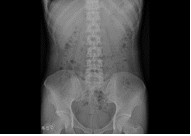

胸部、腹部をはじめ、頭部、椎体(頚椎・胸椎・腰椎)、骨盤、四肢など、全身の骨の撮影を行います。X線を用いて痛みを感じることなく、体の中の様子を調べることができる検査です。病変や骨折などを診断しやすくするため、いろいろな体位、方向から撮影します。 読影(画像診断)は日本放射線学会で認定されている経験豊富な放射線専門医が担当しています。

| 胸部 | 腹部 | 頭 |